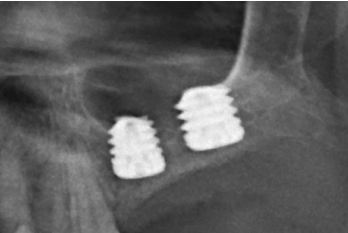

Transcurridos cuatro años, los molares del segundo y tercer cuadrante comienzan a tener una movilidad excesiva y problemas periodontales graves, por lo que se decide la extracción de los mismos y la regeneración de los alveolos con PRGF-Endoret. Una vez regenerada la zona (mes y medio después) se procede a la obtención de un Cone-beam para evaluar el volumen óseo residual. En el mismo se puede observar cómo existe una cresta ósea desigual con zonas de 3,3 mm de altura hasta 7 mm como máximo (Figuras 9 y 10). En esta ocasión, debido al cambio de protocolo descrito anteriormente, se opta por la inserción de implantes extra-cortos de forma directa, ya que los protocolos quirúrgicos para abordar este tipo de situaciones en el año 2011 variaron sustancialmente, siendo estos implantes una herramienta de primera línea para el tratamiento de este tipo de atrofias (Figura 11). Se seleccionan dos implantes extra-cortos (5,5 mm de diámetro x 6,5 mm de longitud para la pieza dental número 26 y 6 mm de diámetro por 5,5 mm de longitud para la pieza dental número 27).